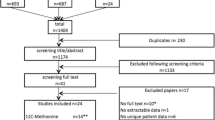

We developed a cohort-level state transition model to evaluate both imaging strategies respecting an intraoperative parathyroid hormone monitored treatment setting as well as a traditional treatment setting. The model reflects patients’ hospital journeys after biochemically diagnosed primary hyperparathyroidism. A cycle length of twelve months and a lifetime horizon were used. We conducted probabilistic analyses simulating 50,000 cohorts to assess joint parameter uncertainty. The incremental net monetary benefit and cost for each quality-adjusted life year were estimated. Furthermore, threshold analyses regarding the tariff of [18F]Fluorocholine PET/CT and the sensitivity of [99mTc]Tc-methoxy isobutyl isonitrile SPECT/CT were performed.

This study was exempt from approval by the local ethics committee as it did not include individual patient data. Instead, all model parameters were obtained from literature evidence or were elicited from an expert panel. Clinical evidence was mainly based on publications from the European Endocrine Surgical Quality Registry (EUROCRINE) including parathyroid diseases [37]. A hospital perspective was adopted in which health-related utilities and direct healthcare costs were covered. For all simulation analyses, R Statistical Software (version 4.2.1) was used [38], with software packages ‘dampack’ and ‘darthtools’ [39, 40]. This study is reported following the Consolidated Health Economic Evaluation Reporting Standards (Online Resource 1) [41].

Imaging strategies

In this study, current best practice is compared with the [18F]FCH PET/CT-based one-stop-shop imaging strategy. In current best practice, [18F]FCH PET/CT is only provided after negative or inconclusive US and MIBI SPECT/CT (Fig. 1a) [9, 10]. In the one-stop-shop strategy, conventional imaging including US and MIBI SPECT/CT will no longer be provided (Fig. 1b) [17, 18]. As described in the 2021 European Association of Nuclear Medicine practice guidelines for parathyroid imaging, preoperative US provides an additional evaluation of the thyroid that might change patient management, especially in the case of coexisting (suspected) malignant nodules [9]. Therefore, in a separate simulation, we slightly adjusted the one-stop-shop strategy by including preoperative US.

Imaging strategies are visualised. The figure shows (a) current best practice [9, 10] compared to (b) the one-stop-shop strategy [17, 18]. In current best practice, [18F]FCH PET/CT is only provided after negative or inconclusive MIBI SPECT/CT. In the one-stop-shop strategy, conventional imaging including US and MIBI SPECT/CT is no longer provided. Abbreviations: PHPT, primary hyperparathyroidism. US, ultrasonography. MIBI SPECT/CT, single-photon emission computed tomography and computed tomography using [99mTc]Tc-methoxy isobutyl isonitrile. [18F]FCH PET/CT, positron emission tomography and computed tomography using [18F]Fluorocholine